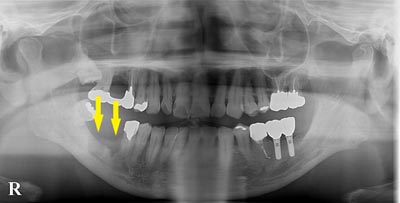

患者様の治療前のレントゲン写真です。写真の黄色矢印部の歯の周囲は、重度の歯周病で大きく歯槽骨が吸収されてしまっていました。そのため、写真の、赤色矢印で示す、下顎骨の中を通る神経までの距離がなく、インプラント埋入には、骨の高さが不足していました。

患者様の治療前のレントゲン写真です。写真の黄色矢印部の歯の周囲は、重度の歯周病で大きく歯槽骨が吸収されてしまっていました。そのため、写真の、赤色矢印で示す、下顎骨の中を通る神経までの距離がなく、インプラント埋入には、骨の高さが不足していました。

患者様のインプラント治療前のレントゲン写真です。右下顎大臼歯2本の抜歯後のレントゲン写真で、写真の黄色矢印は、歯の周囲の歯槽骨が大きく吸収されてしまっていました。

患者様のインプラント治療前のレントゲン写真です。右下顎大臼歯2本の抜歯後のレントゲン写真で、写真の黄色矢印は、歯の周囲の歯槽骨が大きく吸収されてしまっていました。